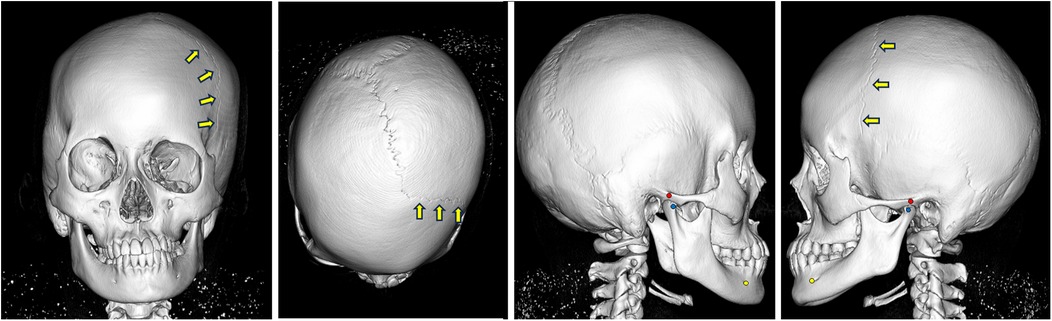

A posteroanterior (PA) cephalogram showed leftward deviation of the chin and a right downward cant of the occlusal plane (Figure 2). Lateral cephalometric analysis indicated a skeletal Class III relationship with a low mandibular plane angle (Supplementary Table 1). The maxillary incisors were labially inclined, whereas mandibular incisor inclination remained within the average range.

Two X-ray images of a skull. The left image shows a front view with three yellow arrows indicating an area on the forehead. The right image displays a side view, also with three yellow arrows pointing to the same region on the skull.

Figure 2. PA and lateral cephalograms taken at the initial examination. Arrows indicate the left coronal suture.